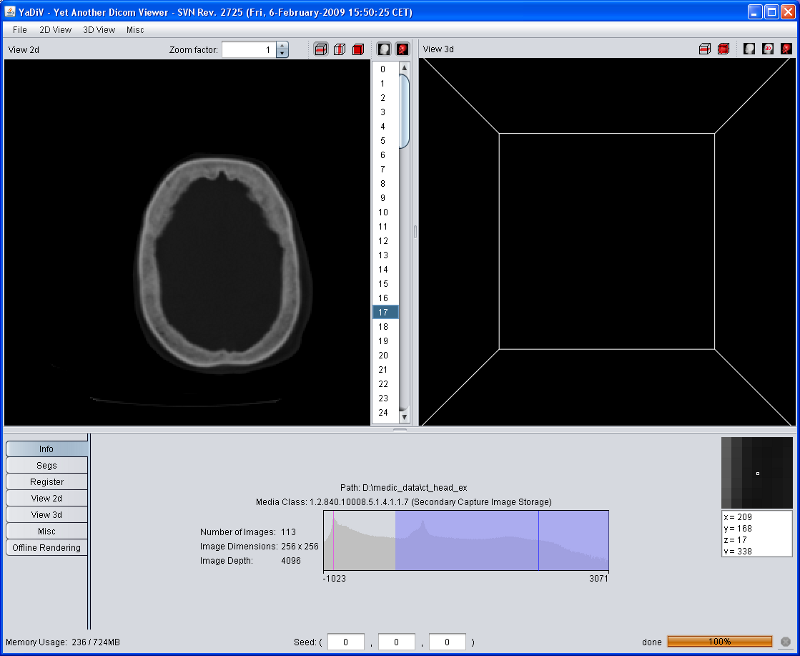

When YaDiV is started, most GUI elements will be disabled. This will change after a DICOM series is loaded. At the moment, YaDiV supports DICOM files with the Photometric Interpretation MONOCHROME2. If you do not have any DICOM files yet, there are some resources in the internet, for example the CT-Cadaver Head or this site.

After loading has finished, the Info Tab of the tool pane displays some short summary of the loaded data, including a voxel data histogram.

The main window of YaDiV shows two elements to explore and analyse the loaded data: the "View 2d" and the "View 3d". Both will display the raw (volume) data as well as segments and other meta info. The volume data rendering is influenced by the selected Region of Interest (ROI), which can be set at the "Misc" panel in the tool pane below.

After a DICOM Series has been loaded, the "View 2d" will automatically show the selected data. Use the Image Selector to select a slice of interest.

The "View 2d" can show slice images in transversal (default), saggital or frontal mode. Switch between the different modes using the "2d View" menu or with the buttons in the "View 2d" title bar.